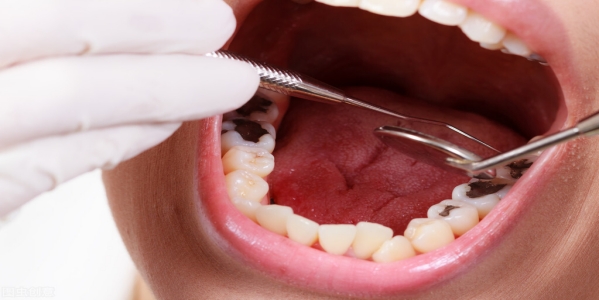

龋齿有什么危害 龋齿是威胁人类身体健康的一种常见病、多发病。根据我国的大量调查发现,我国人民患龋率为37.3%,患龋者平均每人有龋齿2.47颗。由此推算,我国有龋病患者约... 牙齿治疗 鄂昊英 643 2023-11-28

治疗龋齿有什么重要性 龋齿在世界上是常见病、多发病,并且可以诱发出多种慢性疾患。乳牙可以患龋齿,恒牙也可以患龋齿。龋齿是细菌从牙齿感染进入人体内的一个开端。极高的翻齿发病率,使许多牙... 牙齿治疗 仙千风 748 2023-12-19